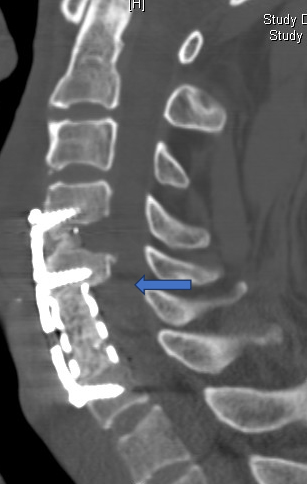

(三)充分减压